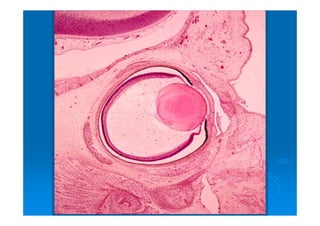

EMBRIOLOGIA DEL OJO

DESARROLLO EMBRIOLÓGICO

CEREBRO ANTERIOR: “COPA OPTICA”

ECTODERMO SUPERFICIAL

Las vesículas ópticas inducen al

MESODERMO Y CRESTA

NEUROECTODERMO DA ORIGEN A: RETINA, CAPAS POSTERIORES DEL IRIS, CUERPO CILIAR Y NERVIO ÓPTICO. SE FORMA DE UNA EVAGINACION DEL CEREBRO ANTERIOR: “COPA OPTICA” su pared externa da origen a epitelio pigmentario y su parte interna al resto.

ECTODERMO SUPERFICIAL DA ORIGENA EL CRISTALINO Y EPITELIO CORNEAL. Las vesículas ópticas inducen al ectodermo superficial a formar la placoda del cristalino, el cual se hunde y forma la fóvea del cristalino.

MESODERMO Y CRESTA NEURAL DA ORIGEN A CAPAS FIBROSA Y VASCULAR DEL OJO. El músculo liso y el tej. Conectivo del cuerpo ciliar derivan del mesodermo. El músculo liso del iris del neuroectodermo y el tej conectivo del iris, la coroides y esclerótica de la cresta neural.